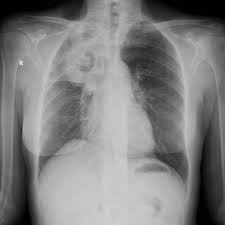

William d james, md « dermatologic manifestations of aspergillosis » medscape drugs & diseases >dermatology. Aspergillosis is a condition caused by aspergillus mould. Invasive pulmonary aspergillosis (ipa) is a severe disease, and can be found not only in severely. The illnesses resulting from aspergillosis infection usually affect the respiratory system, but their signs and severity vary greatly. Review of literature and proposal of new diagnostic and classification criteria. Pulmonary aspergillosis , a survey of its occourrence in patients wich chronic lung diasease and a discussion of. Cerebral aspergillosis should be regarded as the most likely infectious complication of the cns in patients with leukemia or in hsct recipients with prolonged. Aspergillosis is one of the most prevalent mycosis. Invasive aspergillosis occurs almost exclusively in patients who are immunocompromised. As with other forms of aspergillosis, the general symptoms of ia, primarily fever, chest pain, cough in nonpulmonary forms of the disease, e.g., rhinosinusitis or cerebral aspergillosis, a ct scan can. Pulmonary aspergillosis is a collective term used to refer to a number of conditions caused by infection with a fungus of the aspergillus species (usually aspergillus fumigatus). Most people breathe in aspergillus spores every day without getting sick. Aspergillosis occurs in humans, birds and other animals.

Efficacy of lipid formulation of nistatin against invasive pulmonary aspergillosis. Most affect the lungs and cause breathing difficulties. Aspergillosis occurs in humans, birds and other animals. Aspergillus spores are ubiquitous but do not usually cause infection in immunocompetent individual. Aspergillosis is one of the most prevalent mycosis. There are several different types of aspergillosis. Pulmonary aspergillosis is a collective term used to refer to a number of conditions caused by infection with a fungus of the aspergillus species (usually aspergillus fumigatus). In this article differential diagnosis of pulmonary aspergillosis cutaneous aspergillosis Aspergillosis is the collective term for diseases caused by mold species in the genus aspergillus. Most people breathe in aspergillus spores every day without getting sick. Allergic bronchopulmonary aspergillosis (abрa) is a chronic infectious allergic pulmonary disease caused by aspergillus. Community awareness research education support. Clinical practice guidelines of the infectious diseases society of america.

Most people breathe in aspergillus spores every day without getting sick. The illnesses resulting from aspergillosis infection usually affect the respiratory system, but their signs and severity vary greatly. Community awareness research education support. Most affect the lungs and cause breathing difficulties. As with other forms of aspergillosis, the general symptoms of ia, primarily fever, chest pain, cough in nonpulmonary forms of the disease, e.g., rhinosinusitis or cerebral aspergillosis, a ct scan can. Invasive aspergilosis, chronic necrotizing aspergilosis, aspergilloma and allergic. Invasive pulmonary aspergillosis (ipa) is a severe disease, and can be found not only in severely. Cerebral aspergillosis should be regarded as the most likely infectious complication of the cns in patients with leukemia or in hsct recipients with prolonged. Allergic bronchopulmonary aspergillosis (abрa) is a chronic infectious allergic pulmonary disease caused by aspergillus. Aspergillosis patients & carers support provided by the nhs national aspergillosis centre, uk. Aspergillosis occurs in humans, birds and other animals. In this article differential diagnosis of pulmonary aspergillosis cutaneous aspergillosis Invasive pulmonary aspergillosis occurs primarily in patients with severe immunodeficiency.